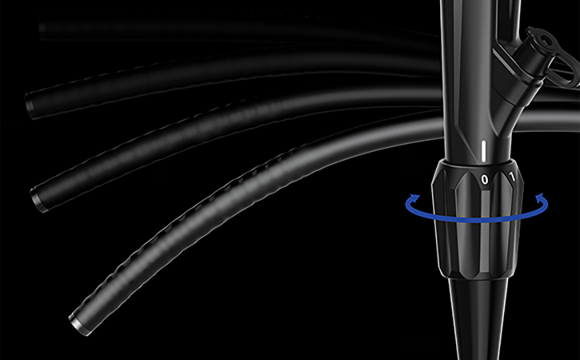

Обзор на 170°Новый колоноскоп серии 50 имеет область обзора 170°, что расширяет диапазон обследования, уменьшает количество слепых зон и, тем самым, снижает частоту ошибочной диагностики кишечных заболеваний. Регулируемая жесткостьВводная трубка колоноскопа имеет функцию многоуровневой регулировки мягкости и жесткости.Вращая регулировочное кольцо, можно изменять мягкость и твердость вводимой части в соответствии с требованиями эндоскопии различных отделов толстой кишки, как того требуют врачи-клиницисты.

Регулируемая жесткостьВводная трубка колоноскопа имеет функцию многоуровневой регулировки мягкости и жесткости.Вращая регулировочное кольцо, можно изменять мягкость и твердость вводимой части в соответствии с требованиями эндоскопии различных отделов толстой кишки, как того требуют врачи-клиницисты. Эластичный изгибВо время эндоскопических процедур он может адаптироваться к различным изгибам толстой кишки. Способен саморегулироваться и поворачивать корпус эндоскопа к просвету в таких областях, как изгиб селезенки и печеночный изгиб, что уменьшает необходимость манипуляций с эндоскопом и повышает комфорт пациента.